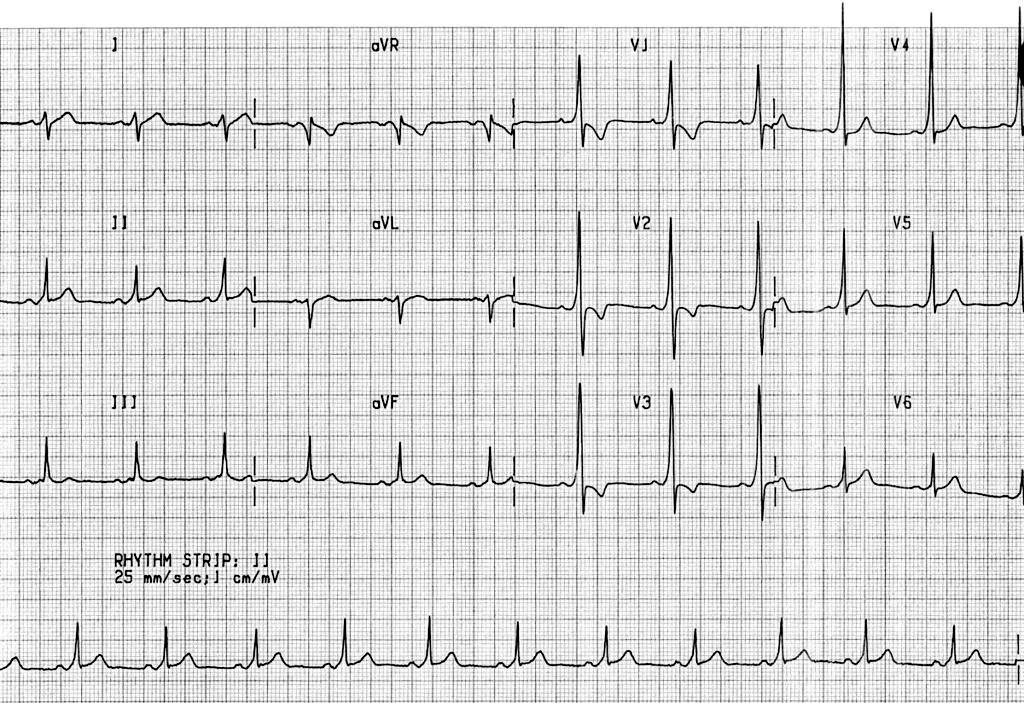

This ECG pattern is diagnostic of? A. Left bundle branch block B. Acute myocardial infarction C. Wolff-Parkinson-White (WPW) syndrome D. Hyperkalemia #NEETPG #MedTwitter Dr. Akhil 🇮🇳 Dr. Priyam Bordoloi Dr. Shiv_Kumar Antonio Arroyo, MD. Medico Cirujano. Dr. Medica🩺 MedLearn Hub Medzonetv

What is the first step in the management of a hemodynamically stable patient with the following rhythm shown on ECG? Options: A. IV Amiodarone B. Carotid massage C. Chest compressions D. Synchronized cardioversion #MedTwitter #Medx Dr. Akhil 🇮🇳 Dr. Priyam Bordoloi Dr. Shiv_Kumar